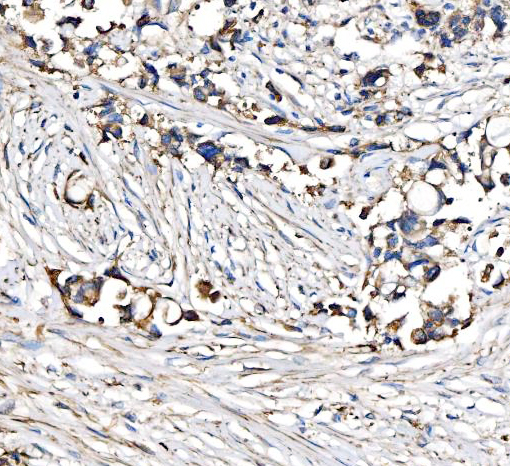

| Gene Name: | CPT1A |

carnitine O-palmitoyltransferase 1, liver isoform; Carnitine O-palmitoyltransferase I, liver isoform; carnitine palmitoyltransferase 1A (liver); Carnitine palmitoyltransferase 1A; carnitine palmitoyltransferase I, liver; CPT I; CPT1; CPT1-LEC 2.3.1.21; CPTI-L; EC 2.3.1; L-CPT1

Strong expression in kidney and heart, and lower in liver and skeletal muscle.

Mitochondrion outer membrane; Multi-pass membrane protein.